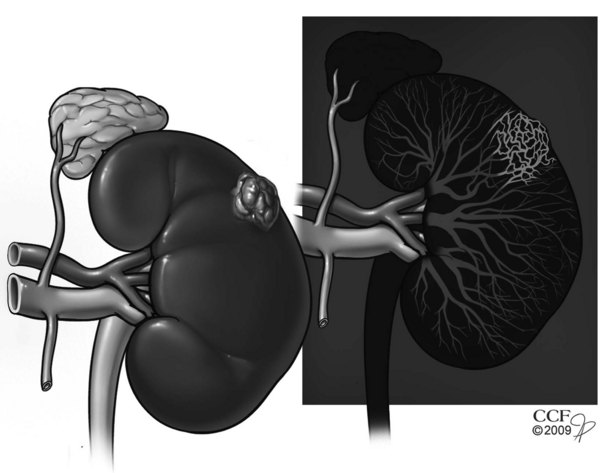

RCC has long been recognized as one of the most vascular of cancers as reflected by the distinctive neovascular pattern exhibited on renal angiography (Fig. 49–10). Dependence on angiogenesis is also suggested by preclinical studies demonstrating blockade of the growth and metastasis of RCC by several well-established antiangiogenic agents (Fujioka et al, 1996; Tan et al, 1996; Dhanabal et al, 1999; Drevs et al, 2000). The primary angiogenesis inducer in clear cell RCC appears to be VEGF, which is suppressed by the wild-type VHL protein under normal conditions and is dramatically upregulated during tumor development (Gnarra et al, 1996; Iliopoulos et al, 1996; Tomisawa et al, 1999; Gunningham et al, 2001; Igarashi et al, 2002; Linehan et al, 2003; Sudarshan and Linehan, 2006; Vira et al, 2007; Lane et al, 2007d). Increased levels of VEGF have been found in the serum and urine of patients with RCC, and a correlation with stage and grade has been reported (Tsuchiya et al, 1998; Chang et al, 2001; Horstmann et al, 2005). Elevated serum levels of basic fibroblast growth factor and other putative angiogenesis inducers for this malignant neoplasm have also been reported in RCC patients compared with normal control subjects (Campbell, 1997; Slaton et al, 2001; Currie et al, 2002; Yagasaki et al, 2003). Functional relevance of VEGF has been demonstrated by studies showing increased levels of VEGF transcript in most hypervascular tumors, whereas the less common hypovascular counterparts exhibit reduced expression of VEGF (Takahashi et al, 1994).

Figure 49–10 Neovascularity associated with renal cell carcinoma. Renal angiogram shows left renal mass exhibiting markedly increased neovascularity within renal tumor.

(Reprinted with permission, Cleveland Clinic Center for Medical Art & Photography © 2007-2009. All Rights Reserved.)